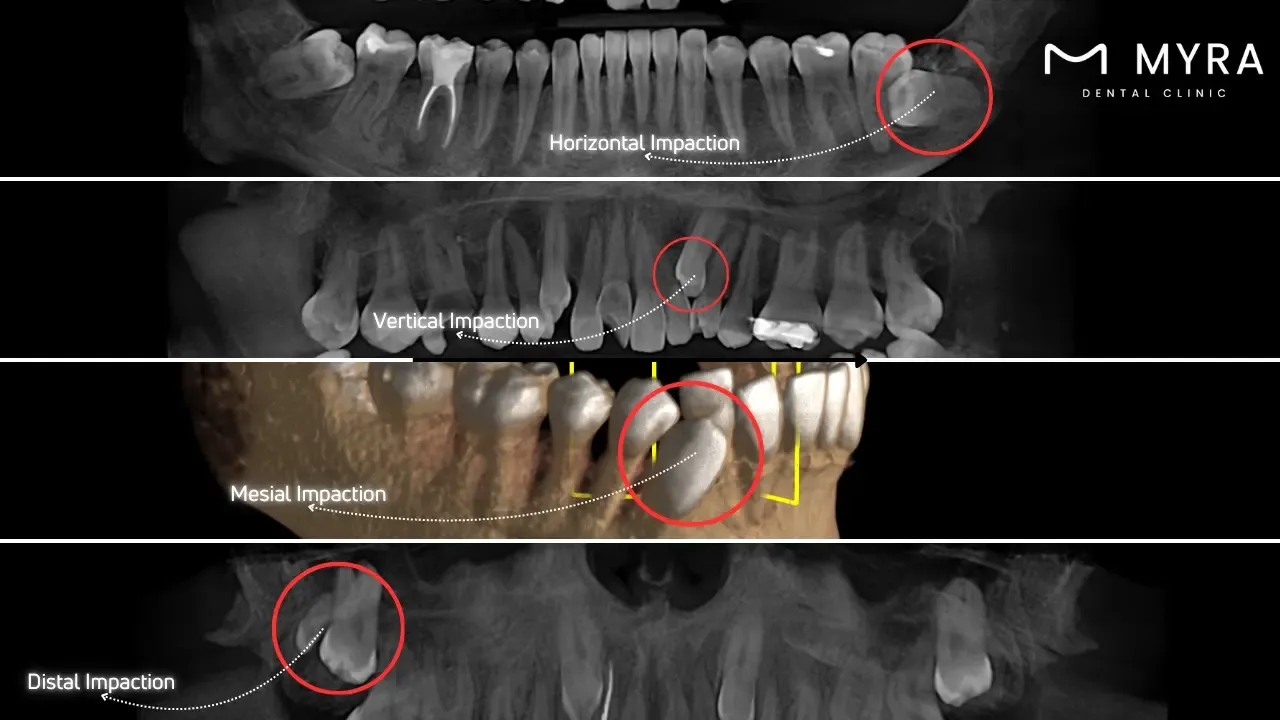

What are the Types of Impacted Teeth?

The types of Impacted Teeth are listed below.

Horizontal Impactions: Horizontal impactions arise if a tooth is positioned sideways within the jaw and lies horizontally instead of vertically. Horizontal impaction causes pressure on the adjacent teeth and leads to pain and misalignment.

Vertical Impactions: Vertical impactions happen when the tooth is correctly oriented but fails to erupt fully through the gum line. The tooth remains submerged in the gum tissue or bone, causing no immediate symptoms but leading to future complications.

Mesial Impactions: Mesial impactions are when the tooth is angled forward, towards the front of the mouth. Mesial impaction pushes against the neighbouring tooth, leading to crowding and discomfort.

Distal Impactions: Distal impactions arise if the tooth is angled reversibly towards the rear of the mouth. The positioning puts pressure on the jaw and surrounding teeth, causing pain and alignment issues.